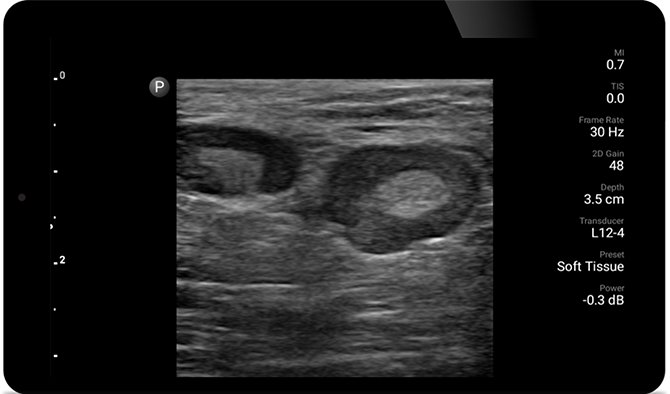

POC ultrasound for soft tissue